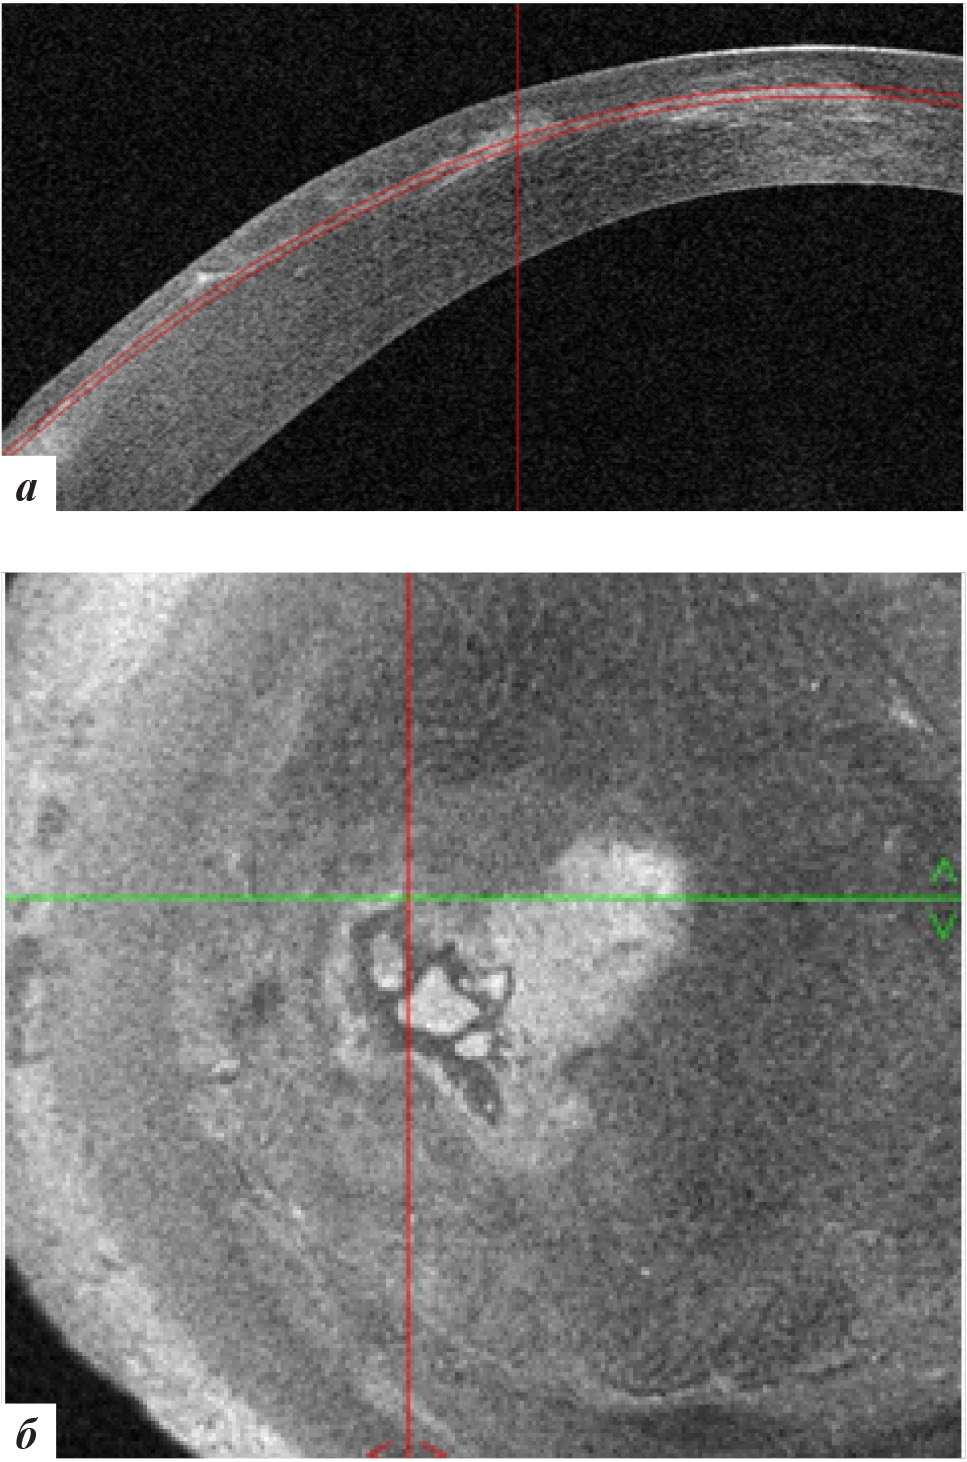

Рис. 4. Данные ОКТ роговицы левого глаза: а – горизонтальная проекция, б – фронтальная проекция

Высота вросшего эпителия по данным ОКТ роговицы уменьшилась (рис. 7). Пациентке было рекомендовано продолжение наблюдения.

Рис. 7. Данные ОКТ роговицы левого глаза через 3 месяца после лечения: а – горизонтальная проекция, б – фронтальная проекция